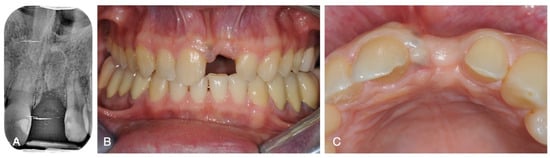

2. Case Report